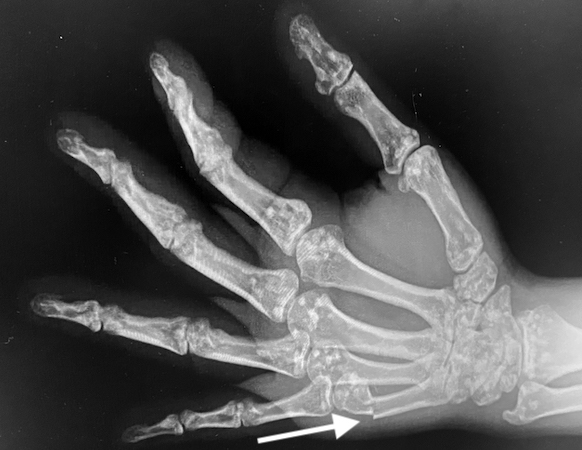

• Osteopoikilosis right hand oblique X-ray with a Boxer's fracture (arrow)

Osteopoikilosis right hand oblique X-ray with a Boxer's fracture (arrow)